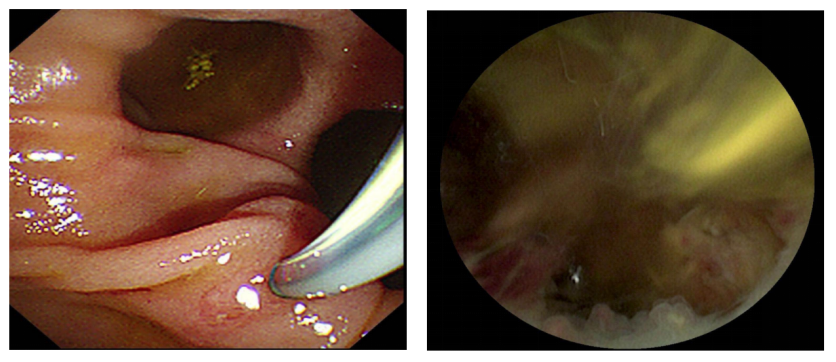

手术当天,首先由麻醉团队进行全身麻醉与监护,冯亚东主任医师团队凭借丰富的临床经验和精湛的操作技术,通过口腔这一自然腔道,将纤细的内镜精准送入胆总管。借助内镜清晰的视野,手术专家成功定位结石位置,随后用钬激光顺利将结石击碎并取出。整个手术过程仅耗时30分钟,且李爷爷体表无任何创口,最大程度降低了手术对老人身体的损伤。术后,重症医学科团队通过密切医学观察与监护,保障了术后安全过渡。经过医护人员精心照料,李爷爷的身体状况日渐好转,不仅高热、腹痛等症状消失,还能正常饮食和活动,精神状态也愈发饱满。